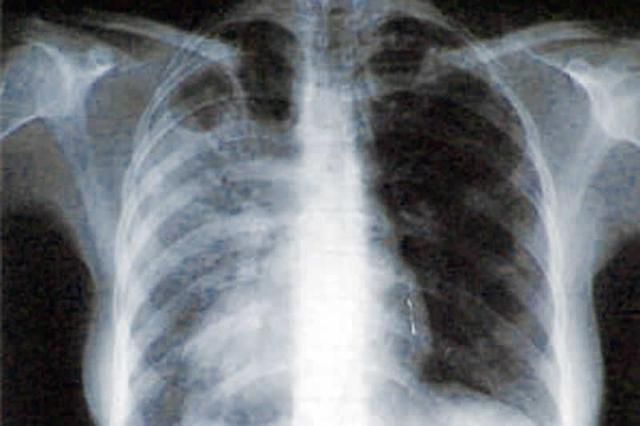

• Tuberculosis (E and A)

Tuberculosis (E and A)

Tuberculosis is an infectious bacterial disease caused by nodules (tubercles) growing in tissues such as lungs. Nodules is a small amout of swelling or aggregation of cells in the human body. Aggregation is a bunch of things grouped together.